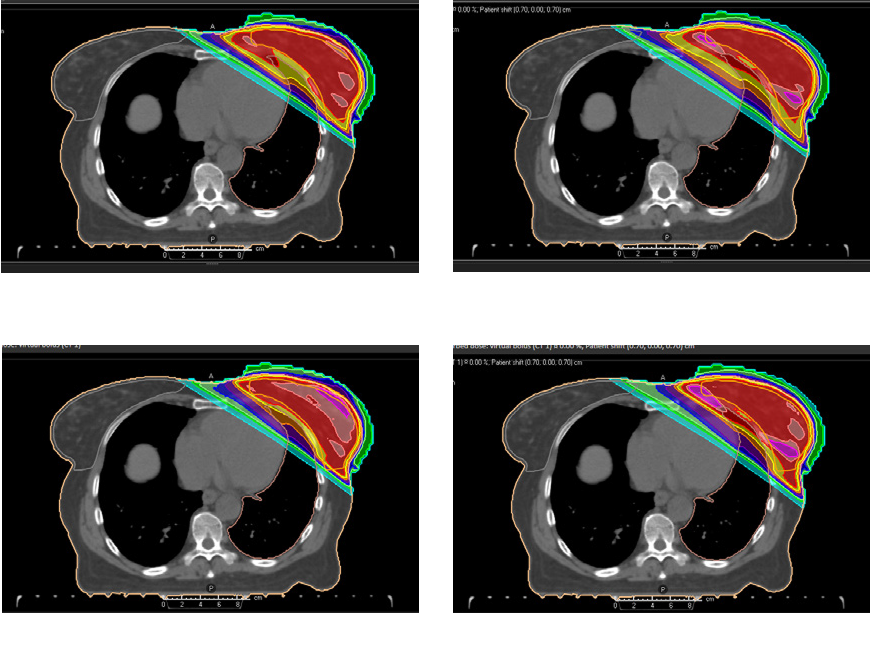

Example 3 (Figure 4)

For a breast case treated with IMRT, robust optimization was used to achieve target coverage in the case of setup variations. It was compared to the virtual bolus method, in which the PTV is extended into the air anterior to the patient, and a virtual bolus is used during planning to prevent optimization to air. Figure 4 shows that robust optimization resulted in more homogeneous target dose and lower skin dose than the virtual bolus method.

Figure 4